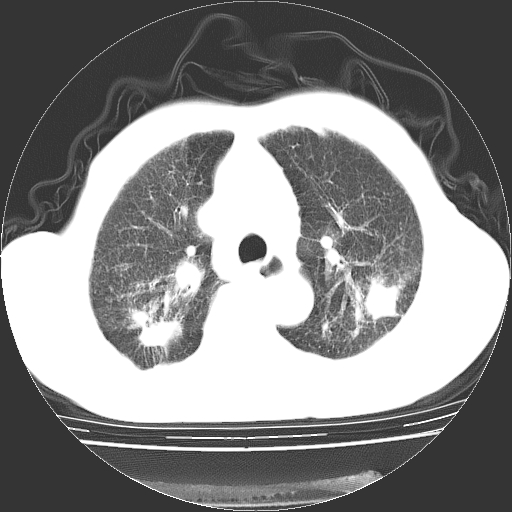

男,72岁,反复咳嗽、憋气一年余,有15年的煤矿井下工作史。

两上肺为主的大小不等结节影伴广泛纤维化,结合病史考虑尘肺。

1、双肺中上叶结节影结合病史考虑巨块型矽肺结节。

2、慢支炎并肺气肿

3、双下肺纤维化灶并左下肺局限性肺气肿。

支持 尘肺,肺心病?-------15年的煤矿井下工作史,双上肺叫对称的片团结节影,内见斑状钙化,边缘见粗长毛刺影,肺纹理混乱,可见网状及磨玻璃样影,肺门纵膈见多个淋巴结钙化